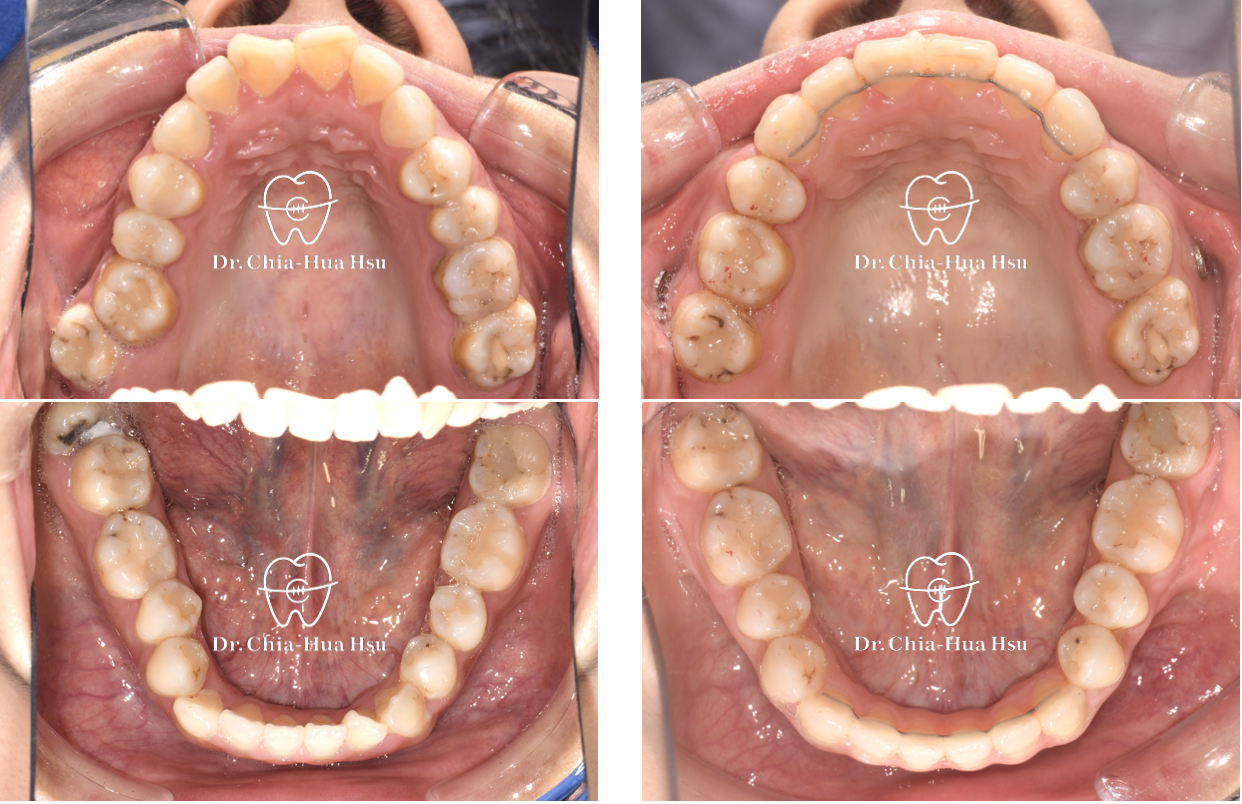

戽斗、前牙錯咬、開咬

成⼈矯正 | ⾦屬矯正 | 正顎⼿術

治療前

治療後